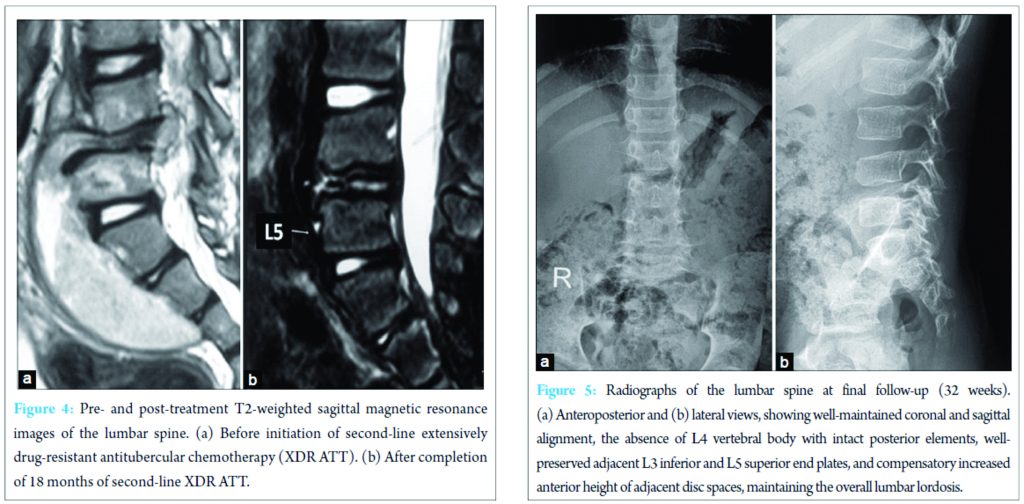

Screening radiographs of the skull, long bones of the limbs, and the rest of the spine were normal. Ultrasound of the abdomen showed 10 cm × 3 cm echo-poor iliopsoas abscess with moving internal echoes, without any organomegaly or other pathologic finding. Magnetic resonance imaging (MRI) showed features suggestive of TB spondylodiscitis with L4 vertebral body destruction, with pre-vertebral and anterior epidural abscess extending from L3 to L5 (Fig. 2). Erythrocyte sedimentation rate (ESR) was raised (40 mm/h), total white blood cell count was 12,800 (normal 4000-11,000/µL) with other blood indices being normal. The clinical and imaging findings ruled out other differential diagnoses such as Langerhans cell histiocytosis, primary or metastatic tumors such as lymphoma or Ewing’s sarcoma as well as any other cause of primary or secondary immunodeficiency. In view of high clinical suspicion, empirical first-line antituberculosis chemotherapy (ATT) was started with isoniazid, rifampicin, pyrazinamide, and ethambutol (Category 1 ATT under Revised National Tuberculosis Program [RNTCP]), given for 6 months with hip spica immobilization. In spite of clinical improvement, repeat radiological evaluation at 6 months showed further collapse of L4 body, significantly increased size of the abscess, now extending from L3 to S2, with signal intensity changes in L3 and L5 vertebral bodies (Fig. 2). Thus, ultrasound-guided percutaneous biopsy of the L4 body and aspiration of the abscess were performed under local anesthesia. Histopathology showed TB granulomatous inflammation and Ziehl–Neelsen stain was positive for acid-fast bacilli. Suspecting a resistant strain of Mycobacterium, streptomycin was added to the regimen while awaiting the culture and drug-sensitivity testing (DST) results. Culture on BACTEC MGIT 960 system using modified Middlebrook 7H9 broth, showed growth of M. tuberculosis complex strain resistant to isoniazid, rifampicin, ethambutol, pyrazinamide, streptomycin, kanamycin, ethionamide, PAS acid, and ofloxacin. The strain showed sensitivity only to Cm (critical concentration-2.5 µg/ml). Repeat radiological evaluation at 8 months, showed destruction extending to L3-4 and L4-5 discs with erosion of L3 and L5 end plates, retrolisthesis of L3 over L5, and abscess extending into the pelvic and gluteal regions (Fig. 2). ESR was raised further (60 mm/h). Second-line ATT comprising of moxifloxacin (Mfx), clofazimine (Cfz), linezolid (Lzd), high-dose isonizid (INH), amoxicillin/clavulanate (Amx/Clv), and PAS, with daily intramuscular Cm was started. At 3 months after initiation, ESR levels decreased (38 mm/hr) and radiology showed consolidation of L3 and L5 bodies and their interspace, with a kyphosis of 10° (Cobb’s method). At 6 months, injectable Cm was stopped while other oral drugs were continued. Physiotherapy and rehabilitation were started with lumbosacral bracing. Second-line ATT was given for a total duration of 18 months (26 months since first presentation to the clinic). The final radiological evaluation showed complete L4 body absence with intact posterior elements with adjacent vertebral endplate consolidation, no clinical or radiological kyphosis, no signs of spinal instability, and complete resolution of the abscess (Fig. 3 and 4). On follow-up at 6 months after completion of ATT (32 months since first presentation), the child walked comfortably, full weight bearing without any orthosis without evidence of back pain or deformity (Fig. 5).